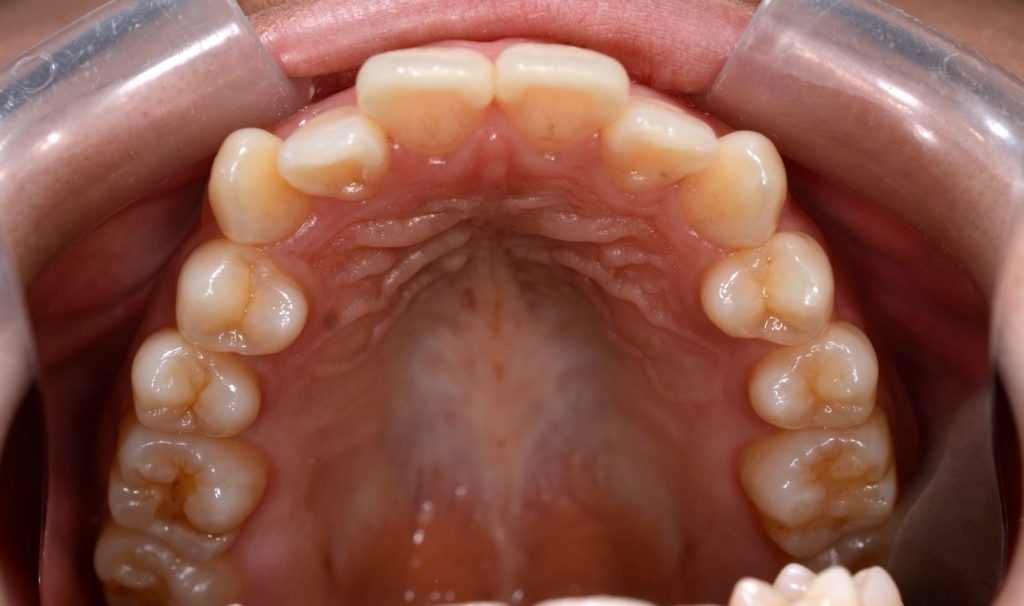

【抜歯】

上下の左右の奥歯を1本ずつ計4本抜歯(すべて前から4番目の第一小臼歯を抜きました)

埋っている智歯は上下とも治療の早期に抜歯予定です

ついでに、歯並びの比較です

上段が矯正治療前、下段が矯正治療後